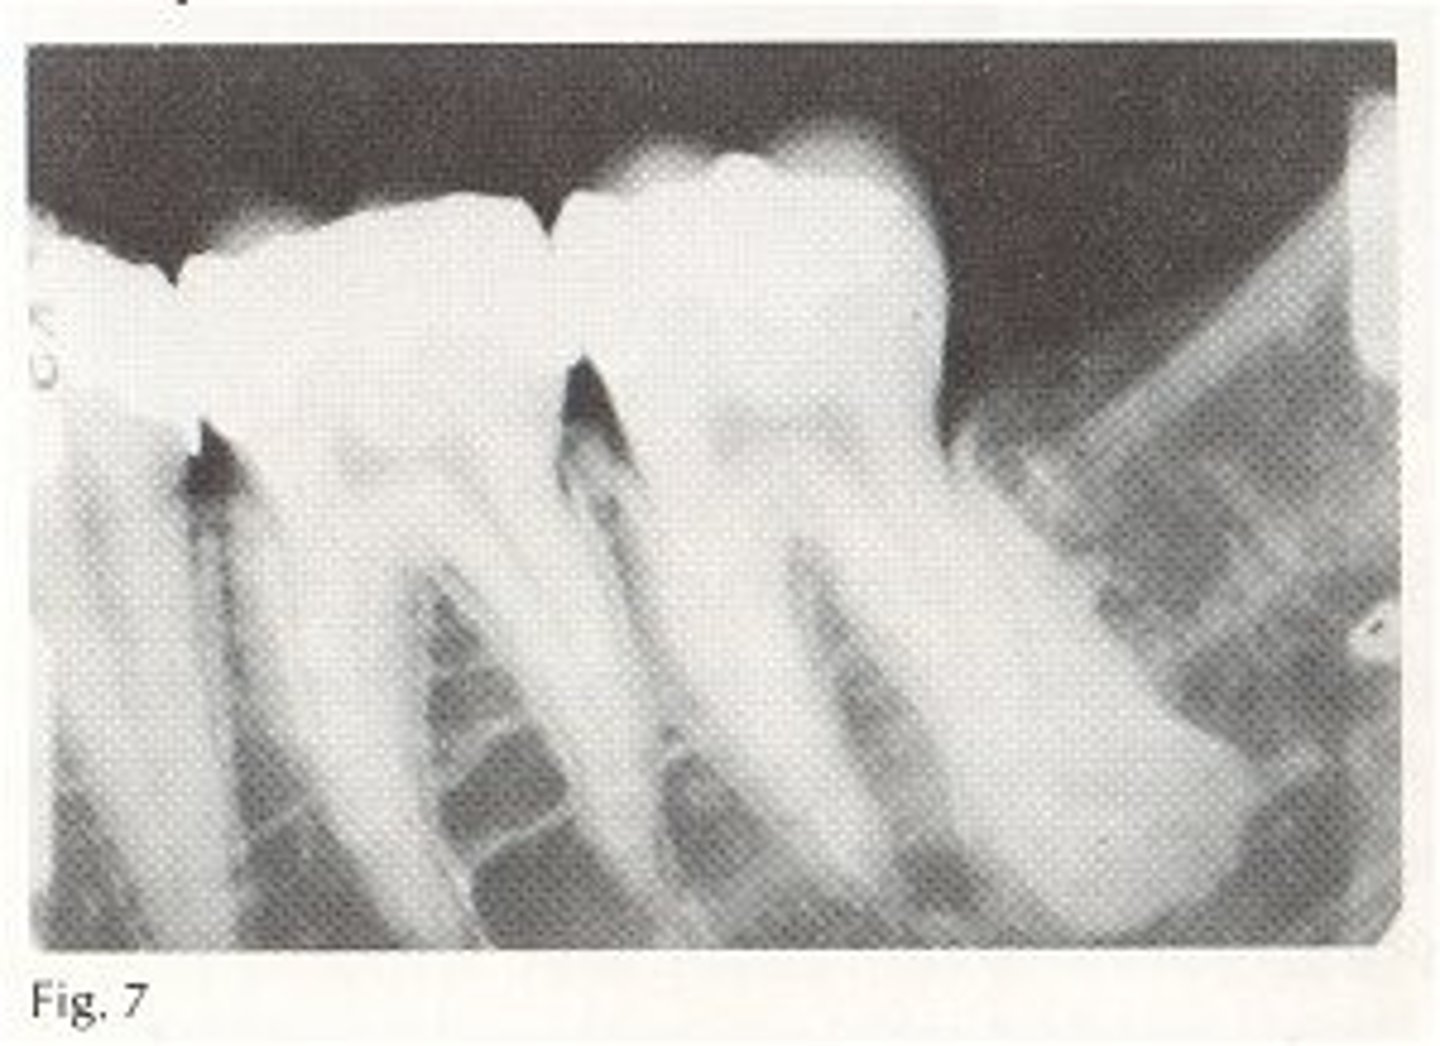

radiographic: mixed opaque lesion w ill-defined borders; symmetrical widening of the PDL; sunburst pattern of bone growth above the crestal bone